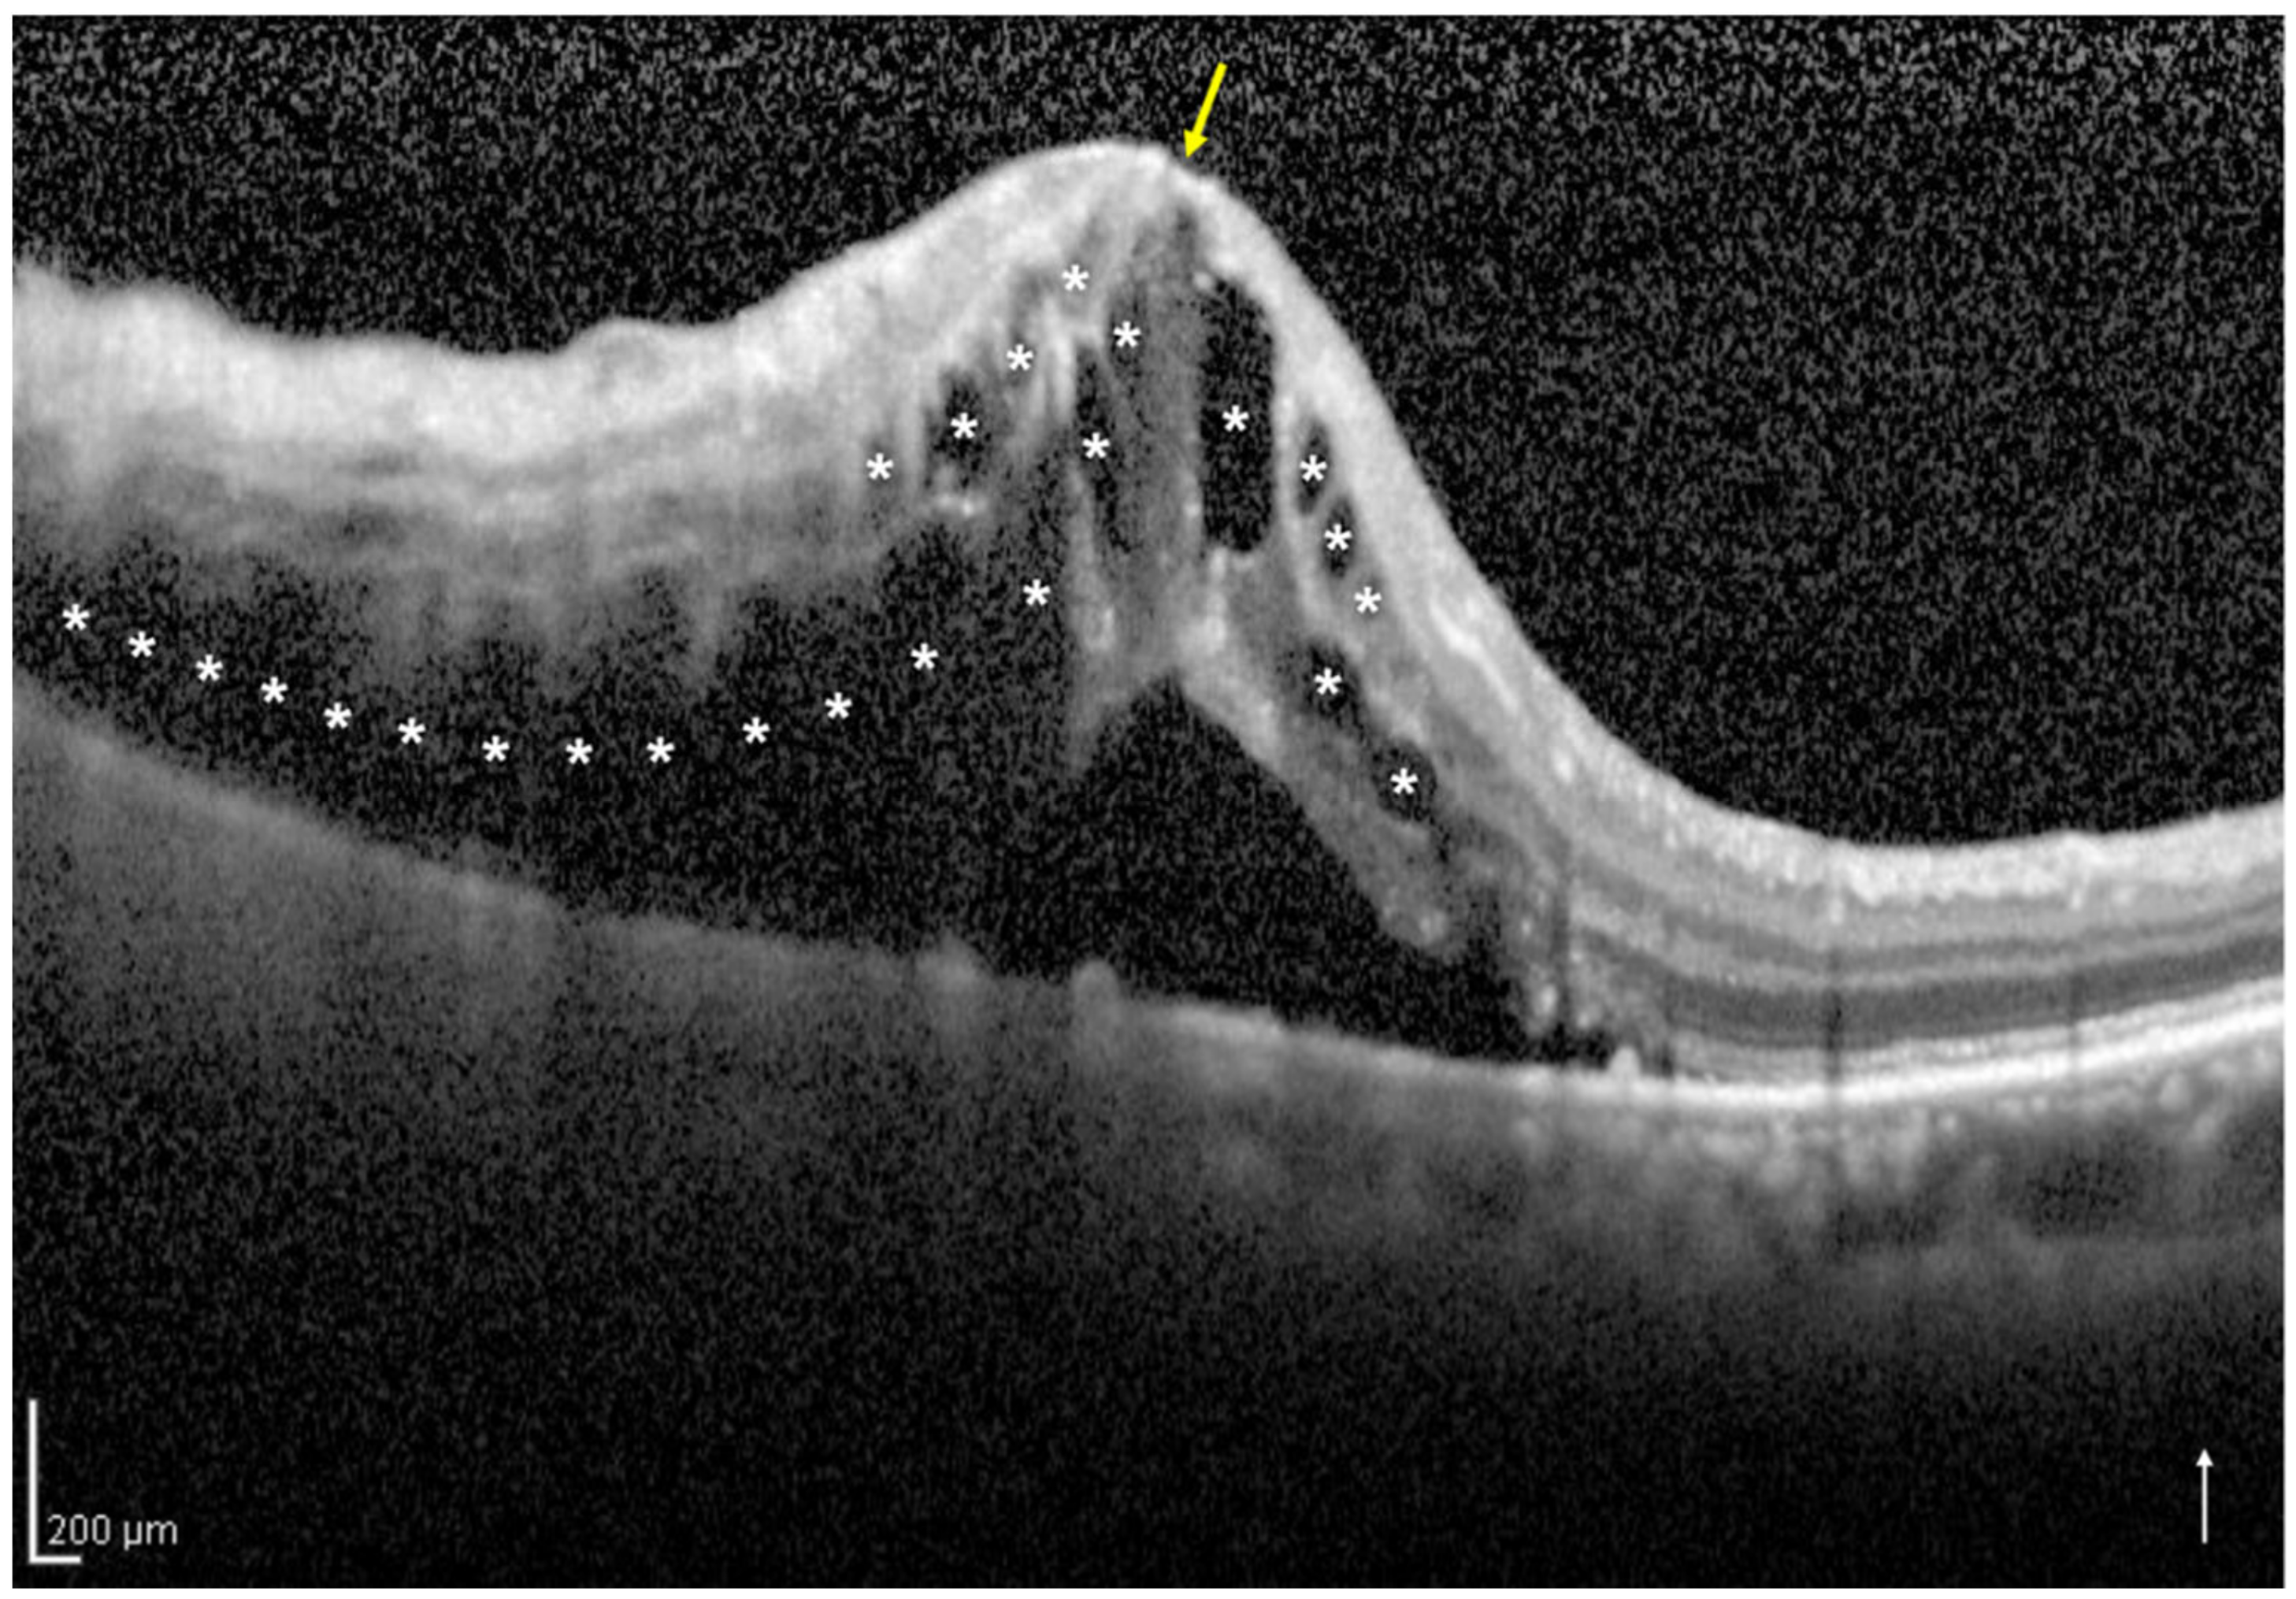

2.3. Definition and Classification of the Two Groups Using Optical Coherence Tomography

| No. of eyes with one-side IRF/both-sides IRF | 33/17 | |

| Central subfield thickness (μm) | 464.5 ± 125.9 | 604.7 ± 109.6 | <0.001 |

| No. of eyes with foveal EZ band disruption (%) | 1 (3.0) | 8 (47.1) | <0.001 |